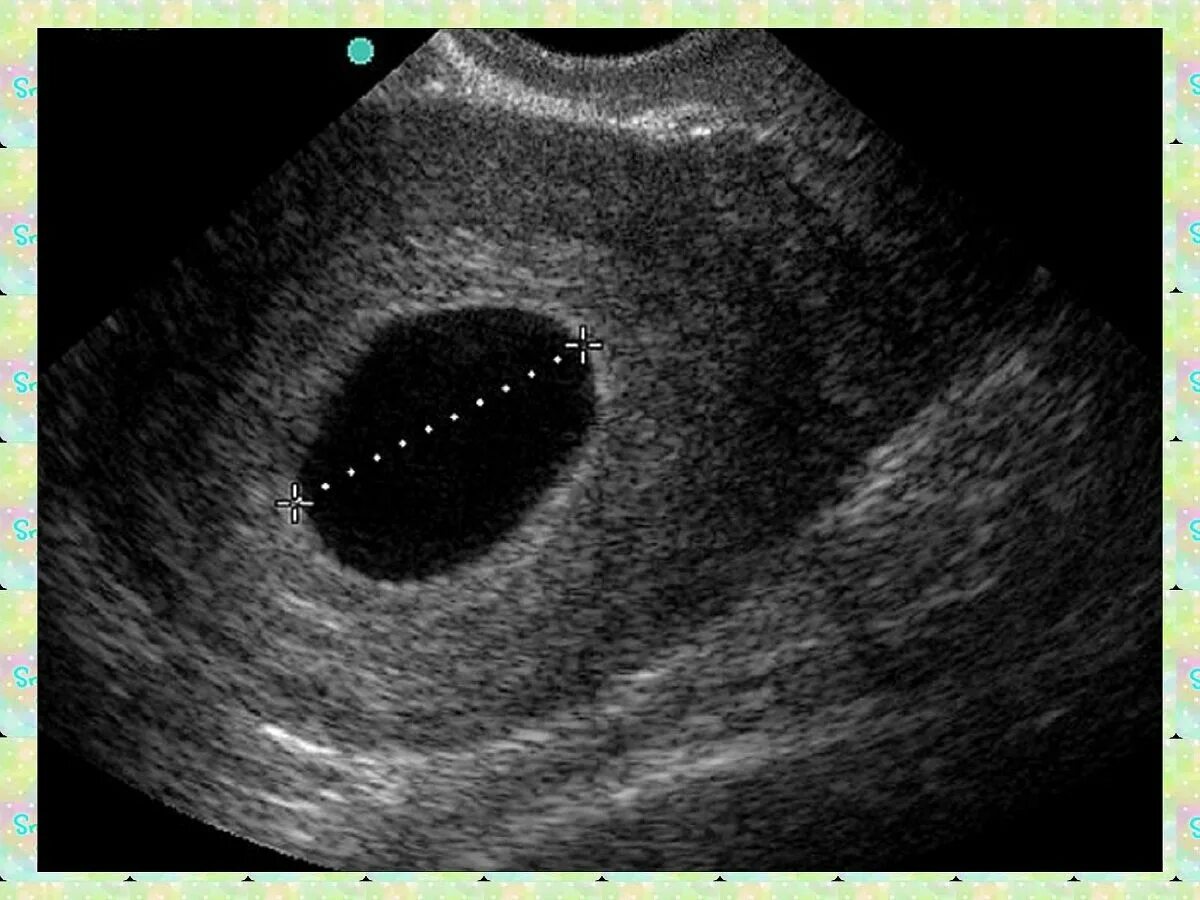

Почему замирает беременность на 6 7